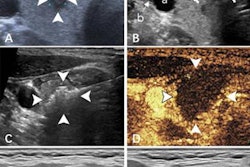

However, they also called for more studies to improve the nomogram's accuracy. The authors wrote that this may be achievable by incorporating "more promising" features from updated technologies. These include elastography, contrast-enhanced ultrasound, and radiomics features among others.